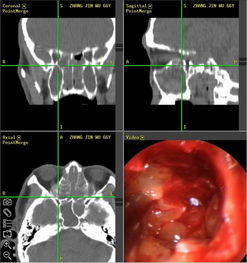

手術

較小的喉嚨息肉可以在表麻下進行纖維喉鏡手術摘除,而較大的喉嚨息肉可以在表麻下行聲帶息肉鉗夾除,但還有一部分病人需要在全麻下行顯微鏡下手術才能完全切除,這個手術是微創手術,不會留下創口。

鼻息肉是贅生於鼻腔或鼻竇黏膜上突起的腫塊。鼻息肉好發於鼻腔的外側壁及鼻頂部;其次為篩竇亦可見於上凳竇部。肉眼觀察鼻息肉呈粉紅色,表面光滑濕潤,觸之相當柔軟,好像剝了皮的熟葡萄。其切面可見擴張的囊腔,腔內積有粉凍狀或灰白色的粘液性分泌物。